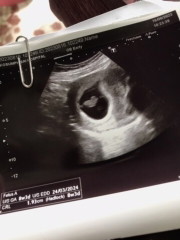

ตั้งครรภ์ท้องแรก

ตั้งครรภ์5สัปดาห์ยังซาวไม่เห็นเด็กเลยค่ะ แม่ๆคนไหนเป็นบ้าง

ของเราไปซาวด์ตอน 6 w หมอก็แนะนำให้ซาวด์ผ่านช่องคลอด เพราะท้องอ่อนซาวด์หน้าท้องจะไม่เห็น เจอต้าวก้อนตัวเล็กมากๆ ได้ยินเสียงหัวใจเต้น (อายหมอนิดหน่อย)

ปกติคะ เพราะปกติแล้วหมอจะแนะนำให้ไปฝากครรภ์ตอนอายุครรภ์8วีคขึ้นไปนะคะเพราะเวลาซาวน์จะเจอหัวใจเด็กแล้วต่ำกว่านั้นจะเจอแค่ถุงเฉยๆค่ะ

ของบ้านนี้5วีคยังไม่เห็นเหมือนกันค่ะแม่ 7วีค เห็นแต่ถุงไข่แดง 8วีค3วัน อัลตราซาวด์เมื่อวานพึ่งเจอน้องพร้อมหัวใจเลยค่ะ แม่ไม่ต้องกังวลนะคะ

บ้านนี้เห็นตอน8สัปดาห์ค่ะตอนนี้ได้24สัปดาห์แล้วค่ะสู้ๆนะคะน้องอาจจะยังตัวเล็กมากยุเลยไม่สามารถอัลตร้าซาวด์เจอน้องได้ค่ะ🥰✌️

อายุครรภ์ยังน้อยค่ะ ของเรา5w ก็ไม่เห็น หมอนัดอีก1เดือนครบ8 w เจอลูก เสียงหัวใจค่า

ปกติงับ 5w เค้าซาวผ่านช่องคลอด เห็นแค่ถุงตั้งครรภ์ ซาวผ่านท้องไม่เห็นอะไรเลย🤣

7wขึ้นไปน้า อย่าพึ่งกังวล บางคน7wก็ยังไม่เห็น น้องตัวเล็กนิดเดียว

เห็นตอนวีค7 หัวใจเต้นรัวๆ น้องโตไม่ถึง 1 ซม